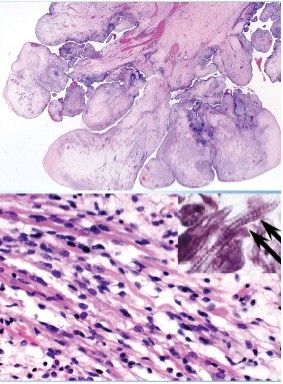

Embryonal rhabdomyosarcoma: rare condition presenting in girls under 4 years. See vaginal bleeding.

Tumor= polypoid, derived from mesenchymal cells; spindle cells containing cross-striations (histology) indicating skeletal muscle origin

Tumor can metastasize- need to treat with radical surgery, chemotherapy